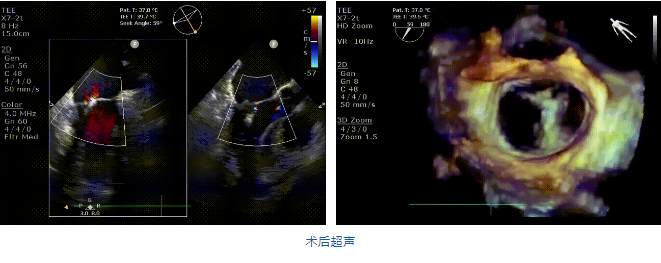

在阜外醫(yī)院潘湘斌教授團(tuán)隊(duì)的支持下,手術(shù)經(jīng)股靜脈-房間隔入路,采用全身麻醉插管,在TEE和DSA引導(dǎo)下完成房間隔穿刺。置入JensClip瓣膜夾系統(tǒng)后,在左房調(diào)整瓣膜夾的位置和軸向,后進(jìn)入左室,在TEE引導(dǎo)下捕捉二尖瓣前后瓣葉,并關(guān)閉瓣膜夾。經(jīng)TEE反復(fù)確認(rèn)手術(shù)效果后最終鎖定并釋放瓣膜夾。術(shù)后即刻超聲顯示瓣膜夾位置穩(wěn)定,功能良好,二尖瓣反流由術(shù)前4+減少至微量,手術(shù)圓滿成功。